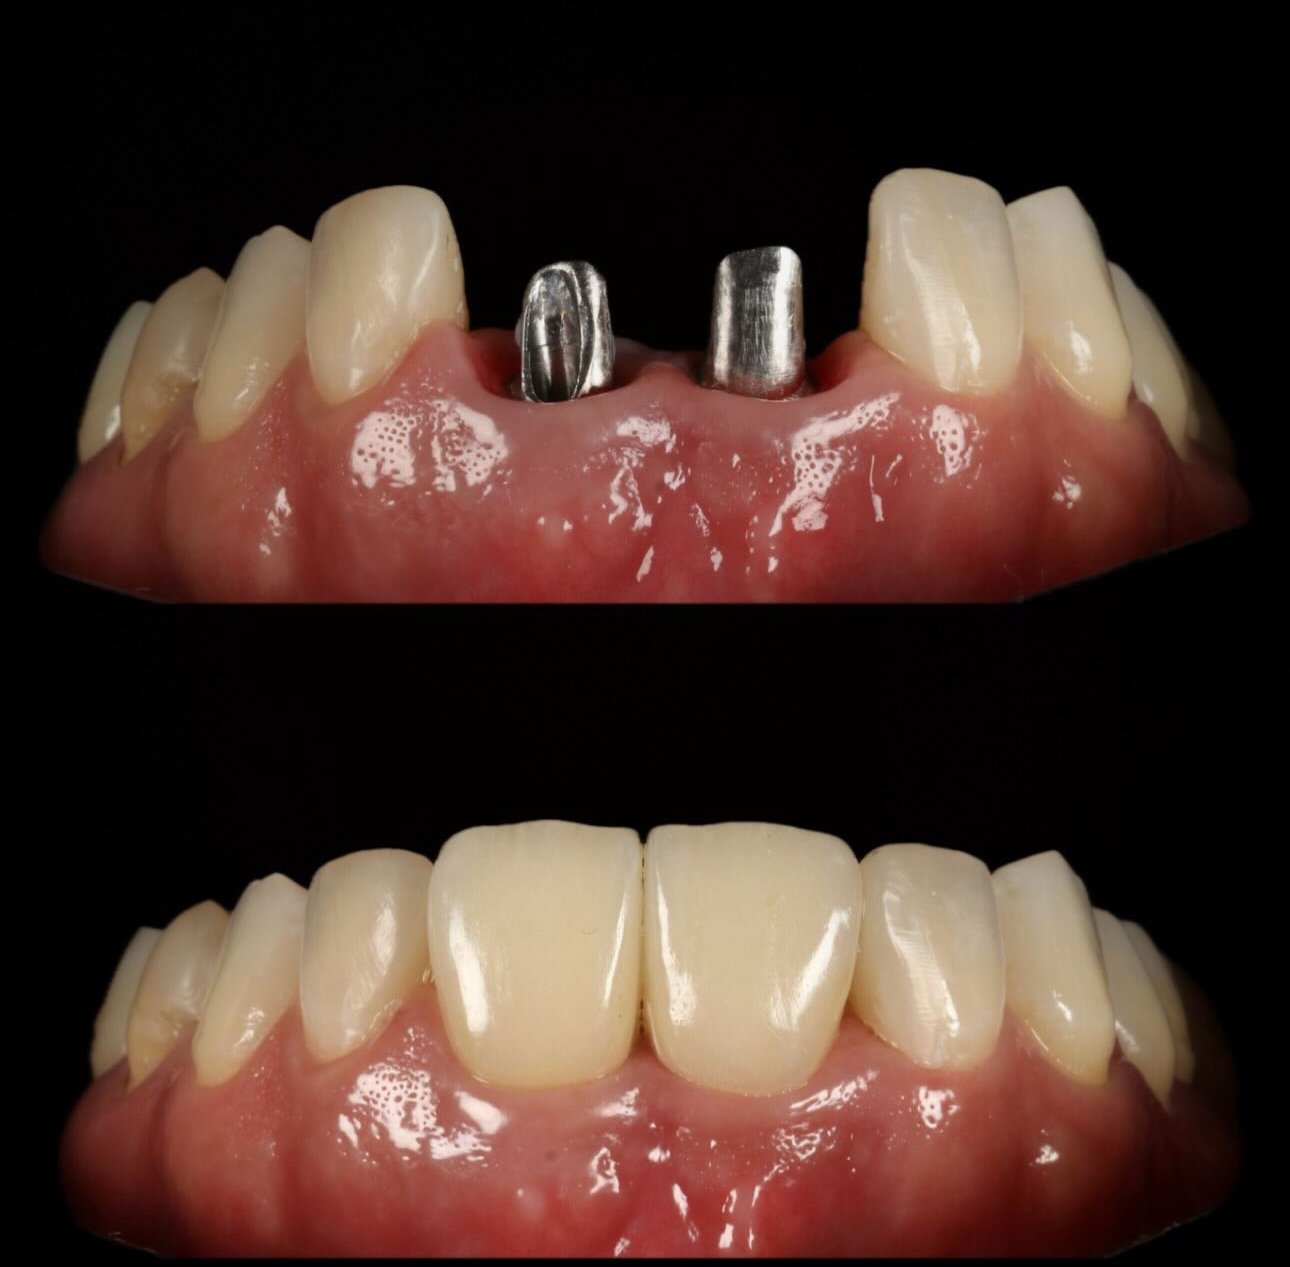

Galería de casos

Algunos resultados obtenidos en nuestra clínica.

Caso implantes 1 Caso implantes 2 Caso implantes 3 Caso implantes 4 Caso implantes 5 Caso implantes 6 Prótesis sobre implantes - Caso 7 Prótesis sobre implantes - Caso 8 Prótesis sobre implantes - Caso 9

Solución avanzada para reemplazar dientes perdidos. Una pieza de titanio se integra al hueso y sirve de base para coronas o prótesis fijas, logrando estabilidad, función y estética natural.

Sí, los implantes se ven completamente naturales. Las coronas se diseñan para que coincidan perfectamente con el color, forma y tamaño de tus dientes naturales.